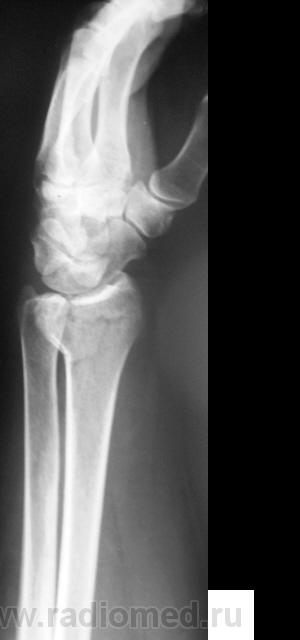

Случай 2. Пациент направлен на рентгенографию лучезапястного сустава.

А вот как трактовать в случае 2 перелом?

В случае 2 - на мой взгляд внутрисуставной перелом задненаружного края дист эпифиза лучевой кости.

Что за +ткань по нар краю эпифиза луча - сложно сказать, мож ломал раньше.